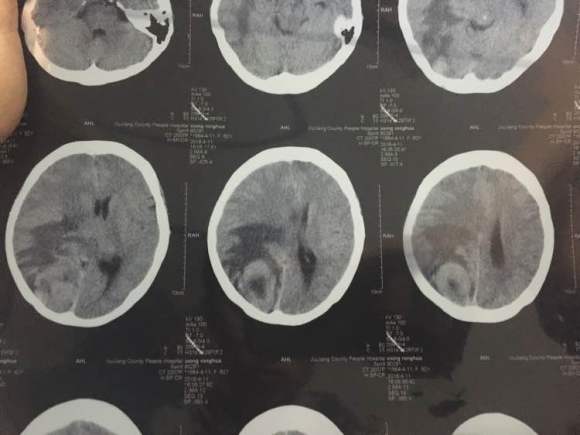

一个人旅行,牵挂的心 02021-10-15 患者家属我婆婆两年前查出肺癌早期,切除两片肺叶,一个月前出现头疼,昨天拍了片子,医生说情况不太好,我这里三四线城市,现在劝她...